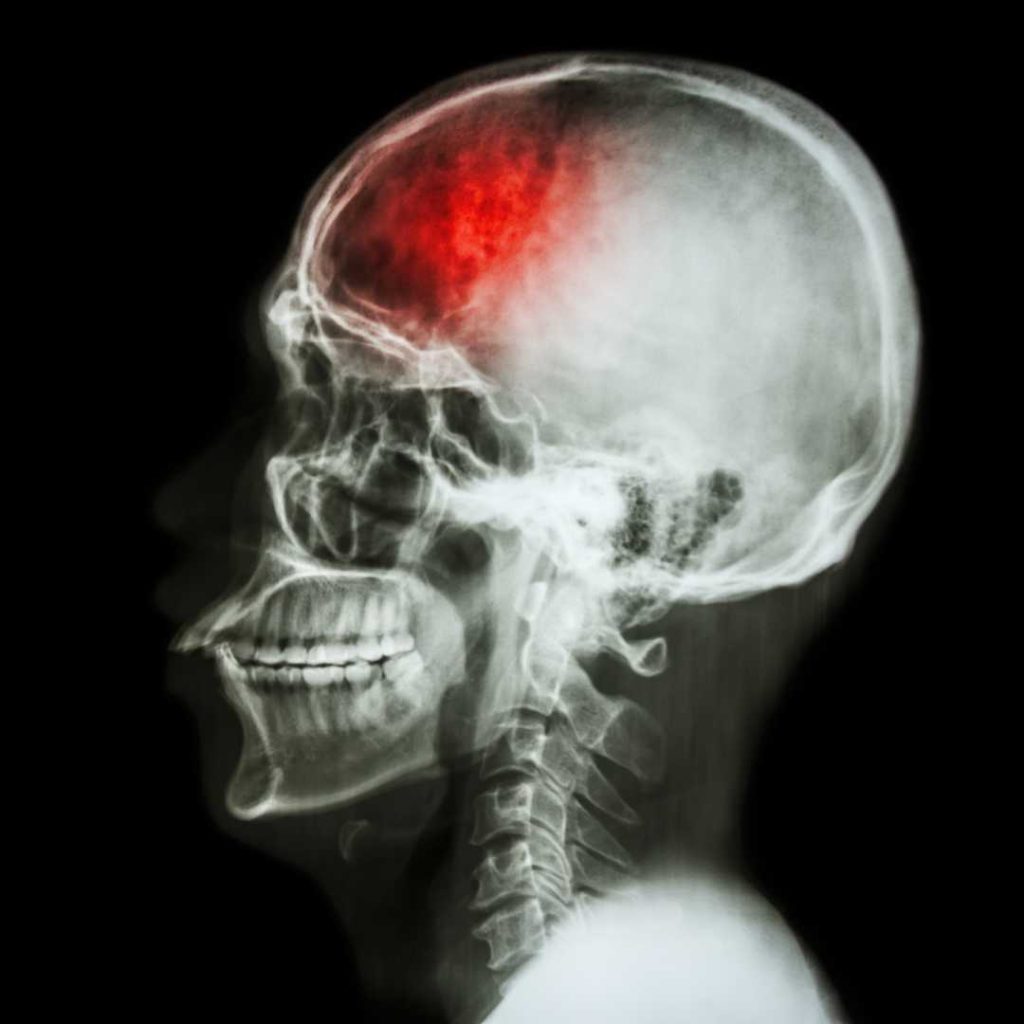

Stroke Often Changes Personality

Of all the areas of life that stroke affects, its impact on the survivor’s personality may be the most difficult for family and friends to understand and get used to. Emotional changes are typical after any type of stroke. Depression is very common after any life-changing health challenge, especially if it results in a loss of independence. Although depression is the most common emotional change after stroke, other psychological or mental changes can make the survivor feel upset or frustrated.